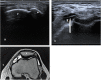

Methods and results: A prospective study was conducted on 143 patients with clinically confirmed AKP. All patients underwent ultrasonography and MRI examinations of the knee. The diagnostic accuracy of ultrasonography compared to MRI for evaluating different findings of possible causes of AKP were analyzed using receiver operating characteristic (ROC) curve and judged by area under curve (AUC). A total of 155 knees were included in the study; 26 knees showed no abnormalities, 19 knees showed positive MRI only, and 110 knees showed positive ultrasonography and MRI. Ultrasonography and MRI reported 11 different findings of possible causes of AKP or related to it. Joint effusion was the most common finding (38%) followed by trochlear cartilage defect (20.6%) and superficial infrapatellar subcutaneous edema (20%). The overall accuracy of ultrasonography was 85.3% sensitivity and 100% specificity. The ultrasonography provided the highest sensitivity (100%) in detecting bipartite patella, followed by 91.5% for joint effusion, and 87.5% for quadriceps tendinopathy. The ROC curve analysis of overall accuracy of ultrasonography showed an AUC of 0.93. The overall Kappa agreement between ultrasonography and MRI was good (k = 0.66).